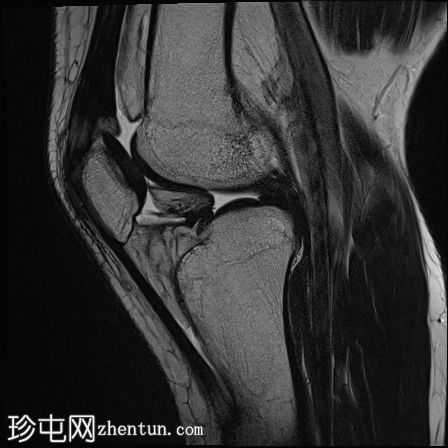

冠状面

T1

股骨内侧髁发育不全

胫骨髁间棘发育不全

腓骨头发育不全

前交叉韧带(ACL)和后交叉韧带(PCL)发育不全

髌腱延长,低位插入。

腘绳肌腱起源异常

外侧胫骨半月板韧带增厚;与外侧韧带(LCL)连接

术后可能出现股四头肌腱改变

本病例展示了腓骨半肢畸形(I型)的特征性表现。然而,腓骨半肢畸形可能伴有多种其他异常及异常组合,包括本例中的十字韧带发育不良。本文所述结果仅代表该疾病的一种可能变体。